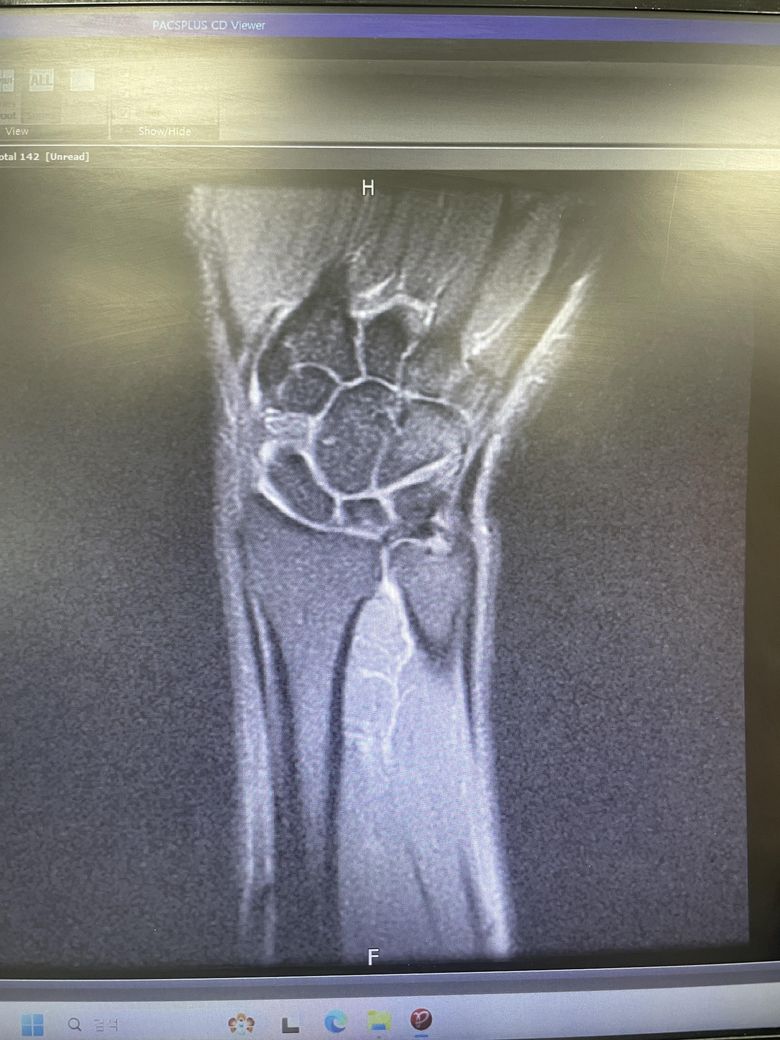

tfcc 파열진단 받았습니다. MRI 판독좀 부탁드립니다.

1A 1B 1C 중 어디에 해당하는지 알고 싶고

파열정도가 심한건지 궁금합니다.

아니면 보존적 치료(주사)로 괜찮은지.. 관절경 봉합술을 해야하는지..

MRI상 TFCC 부위에 고강도 신호가 보이고 파열이 의심됩니다. 통증이 40일 이상 지속되고 있어 보존치료 효과가 낮을 수 있습니다.

관절경 수술로 손상부위를 봉합하면 회복과 재발 방지에 도움이 됩니다. 스포츠 손상 전문 정형외과에서 수술 여부를 재평가받는 것이 좋습니다!